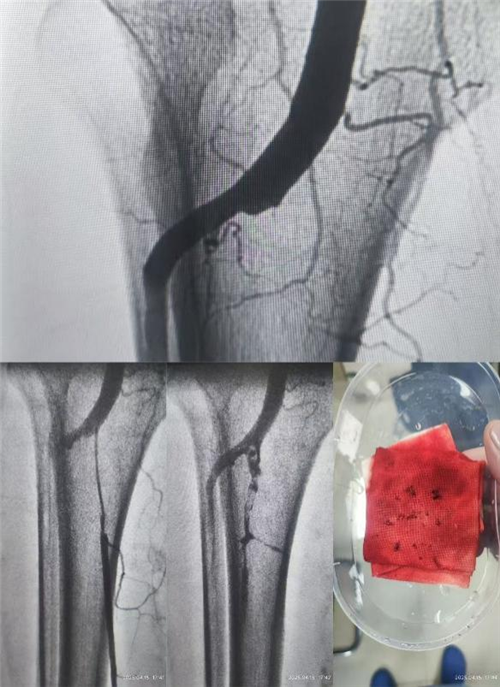

入院次日下午16:40,手术团队争分夺秒,为两位患者实施左下肢动脉造影+导管内吸栓+下肢动脉导管溶栓术。术中,大量陈旧性血栓被成功吸出!一小时后返回病房,两位患者惊喜地感叹:“双腿暖和多了,麻木感也减轻了不少!”随后,左侧腹股沟留置溶栓导管,开启溶栓抗凝治疗。

第一期手术